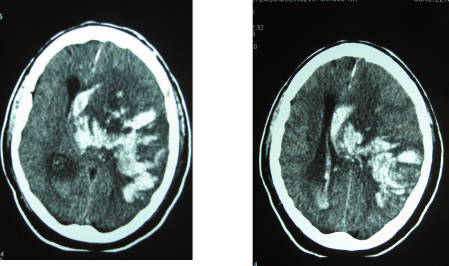

En este caso se trata de un paciente que presenta una hemorragia sintomática en la zona de isquemia con una TAC cerebral inicial normal con dos horas de evolución desde el inicio de los síntomas:

Y la TAC cerebral a las 24 horas: